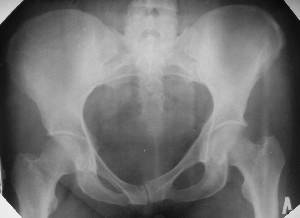

Уважаемые коллеги! Хотел-бы обсудить интерессный, на мой взгляд, случай.На консультацию пришла женщина 45 лет с отводящей контрактурой правого бедра.

Из анамнеза: в ноябре 2002г. оступилась,упалана трап самолета (на верхней площадке, сразу при выходе из салона) на правый тазобедренный сустав, а затем - вниз на землю на ноги и ягодицы. Потеряла сознание от боли. Доставлена в больницу по месту жительства, лечилась консервативно с диагнозом кокцигодиния.На рентгенограмме от 27.11.02г. вывиха копчика не определяется (снимок идентичен представленной R-грамме от28.11.03г., кроме этого есть нормальная R-грамма копчика в боковой проекции).Через три недели стала ходить, но привести правую ногу в тазобедренном суставе не могла. Сейчас ходит отведя кнаружи правое бедро и голень, как ножку циркуля (фото 1). Неврологических нарушений нет. По просьбе врачаможет на 30-40 секунд поставить ноги вместе (фото 2). При этом испытывает сильную тянущую боль и ощущение "вывернутости" в правом тазобедренном суставе. Эти ощущения заставляют вновь отвести бедро. В положении лежа разогнуть бедро полностью не может из-за болей в ягодичной мышце (фото 3). Сгибание также ограничено из-за болей (фото 4). Отведение в положении лежа возможно в том же объеме, что и стоя (фото 5). Заподозрен старый разрыв правого крестцово-подвздошного сочленения.Выполнено R-исследование и КТ(в приложении). По-поводу деформации лонного сочленения выяснен гинекологический анамнез. Роды одни, нормальные в 22 года. Из роддома выписана на 8 сутки, нарушения походки не было, R-графия таза не проводилась. Вопросы на обсуждение: 1. Диагноз либо алгоритм дальнейшего обследования. 2. Лечебная тактика (в первую очередь возможность и целесообразность оперативного лечения).

Уважаемый Юрий Алексеевич, сделаны ли пациентке более дистальные срезы КТ с захватом области тазобедренного сустава? Учитывая давность травмы, могли присоединиться и дистрофические процессы в субхондральной кости головки и впадины. Изменения в капсуле будут хорошо видны на УЗИ, особенно в сравнении со здоровой стороной. Эффективность лечебно-диагностического введения гормональных препаратов, на мой взгляд, сомнительна ввиду давности патологического состояния. При такой стойкой и давней контрактуре без операции вряд ли можно обойтись. Под наркозом амплитуда на разгибание должна увеличиться, усилить эффект можно тено-миотомиями заинтересованных групп мышц, капсулотомией + в послеоперационном периоде хорошее консервативное противовоспатлительное лечение с укладками на разгибание.Что мешает приведению пока не ясно, во встретившихся в нашей работе аналогичных ситуациях причиной был формирующийся медиальный остеофит головки, выталкивающий её из впадины.

эластичности этих мышц. В положении приведения происходит их перерастяжение, создается болевой синдром. На представленных снимках, к сожалению, эти структуры не определяются.